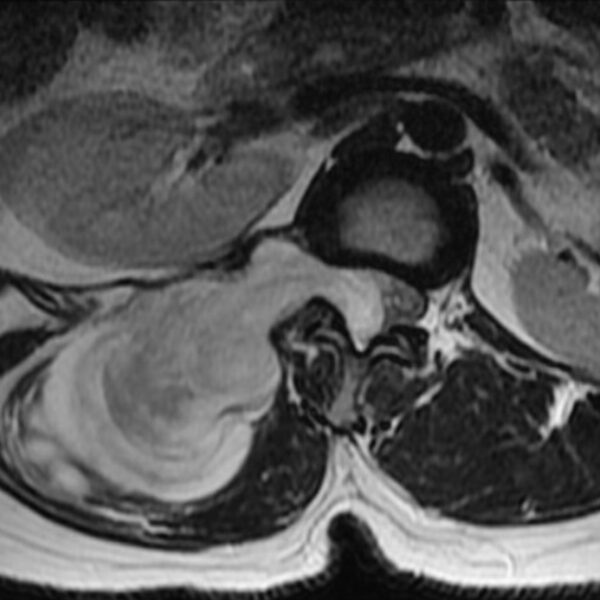

MRI

Showing 1–9 of 86 results